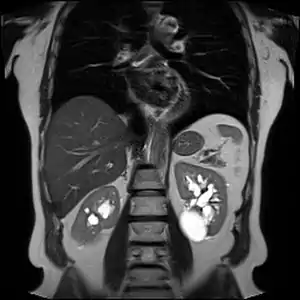

Numerous renal cysts are seen in the cystic kidney diseases, which include polycystic kidney disease and medullary sponge kidney.

Advanced polycystic kidney disease with multiple cysts.[12]